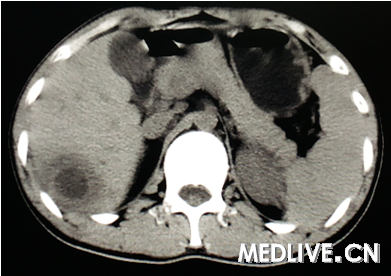

男,26岁,右上腹部疼痛伴畏寒发热3天。

图4为CT增强扫描延迟期。

右上腹痛伴畏寒发热提示有感染存在,CT为囊性病变,动脉期囊腔周围有水肿,静脉期囊腔边缘增强,囊内无增强排除血管瘤;囊内无子囊,无分隔可排除肝包虫感染。最终诊断为肝脓肿。

诊断:肝脓肿。 依据:发热,畏寒考虑感染性疾病,患者右上腹疼,上腹部CT肝右叶可见空腔,周围水肿带,增强可见强化,符合肝脓肿影像。 鉴别:肝囊肿并感染,肝结核。

上腹痛伴畏寒发热提示有感染存在,排除肝囊肿;CT示球形囊性病变,动脉期囊腔周围有水肿,静脉期囊腔边缘增强,囊内无增强排除血管瘤;囊内无子囊,无分隔可排除肝包虫感染。诊断考虑肝脓肿。

CT可见肝内囊性病变,边界清,囊内呈液性暗区(无增强),无分隔,囊腔周围有水肿,综合上述CT表现诊断为肝脓肿。